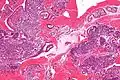

Coupe histologique de l'endomètre vue au microscope optique

L'endomètre consiste en une couche simple d'épithélium cylindrique sur un tissu conjonctif, ce dernier étant aussi appelé stroma dans la littérature scientifique. L'épaisseur de ce tissu conjonctif évolue en fonction des niveaux d'hormones. A l'intérieur de l'utérus, des glandes cylindriques simples vont de la surface de l'endomètre jusqu'à la base du tissu conjonctif, qui acheminent aussi un apport sanguin depuis les artères spiralées utérines. Chez une femme en âge de procréer, deux couches d'endomètre peuvent être distinguées. Ces deux couches sont présentes uniquement à l'intérieur de l'utérus, et non à l'intérieur des tubes utérins (anciennement appelés trompes de Fallope)[4],[5].